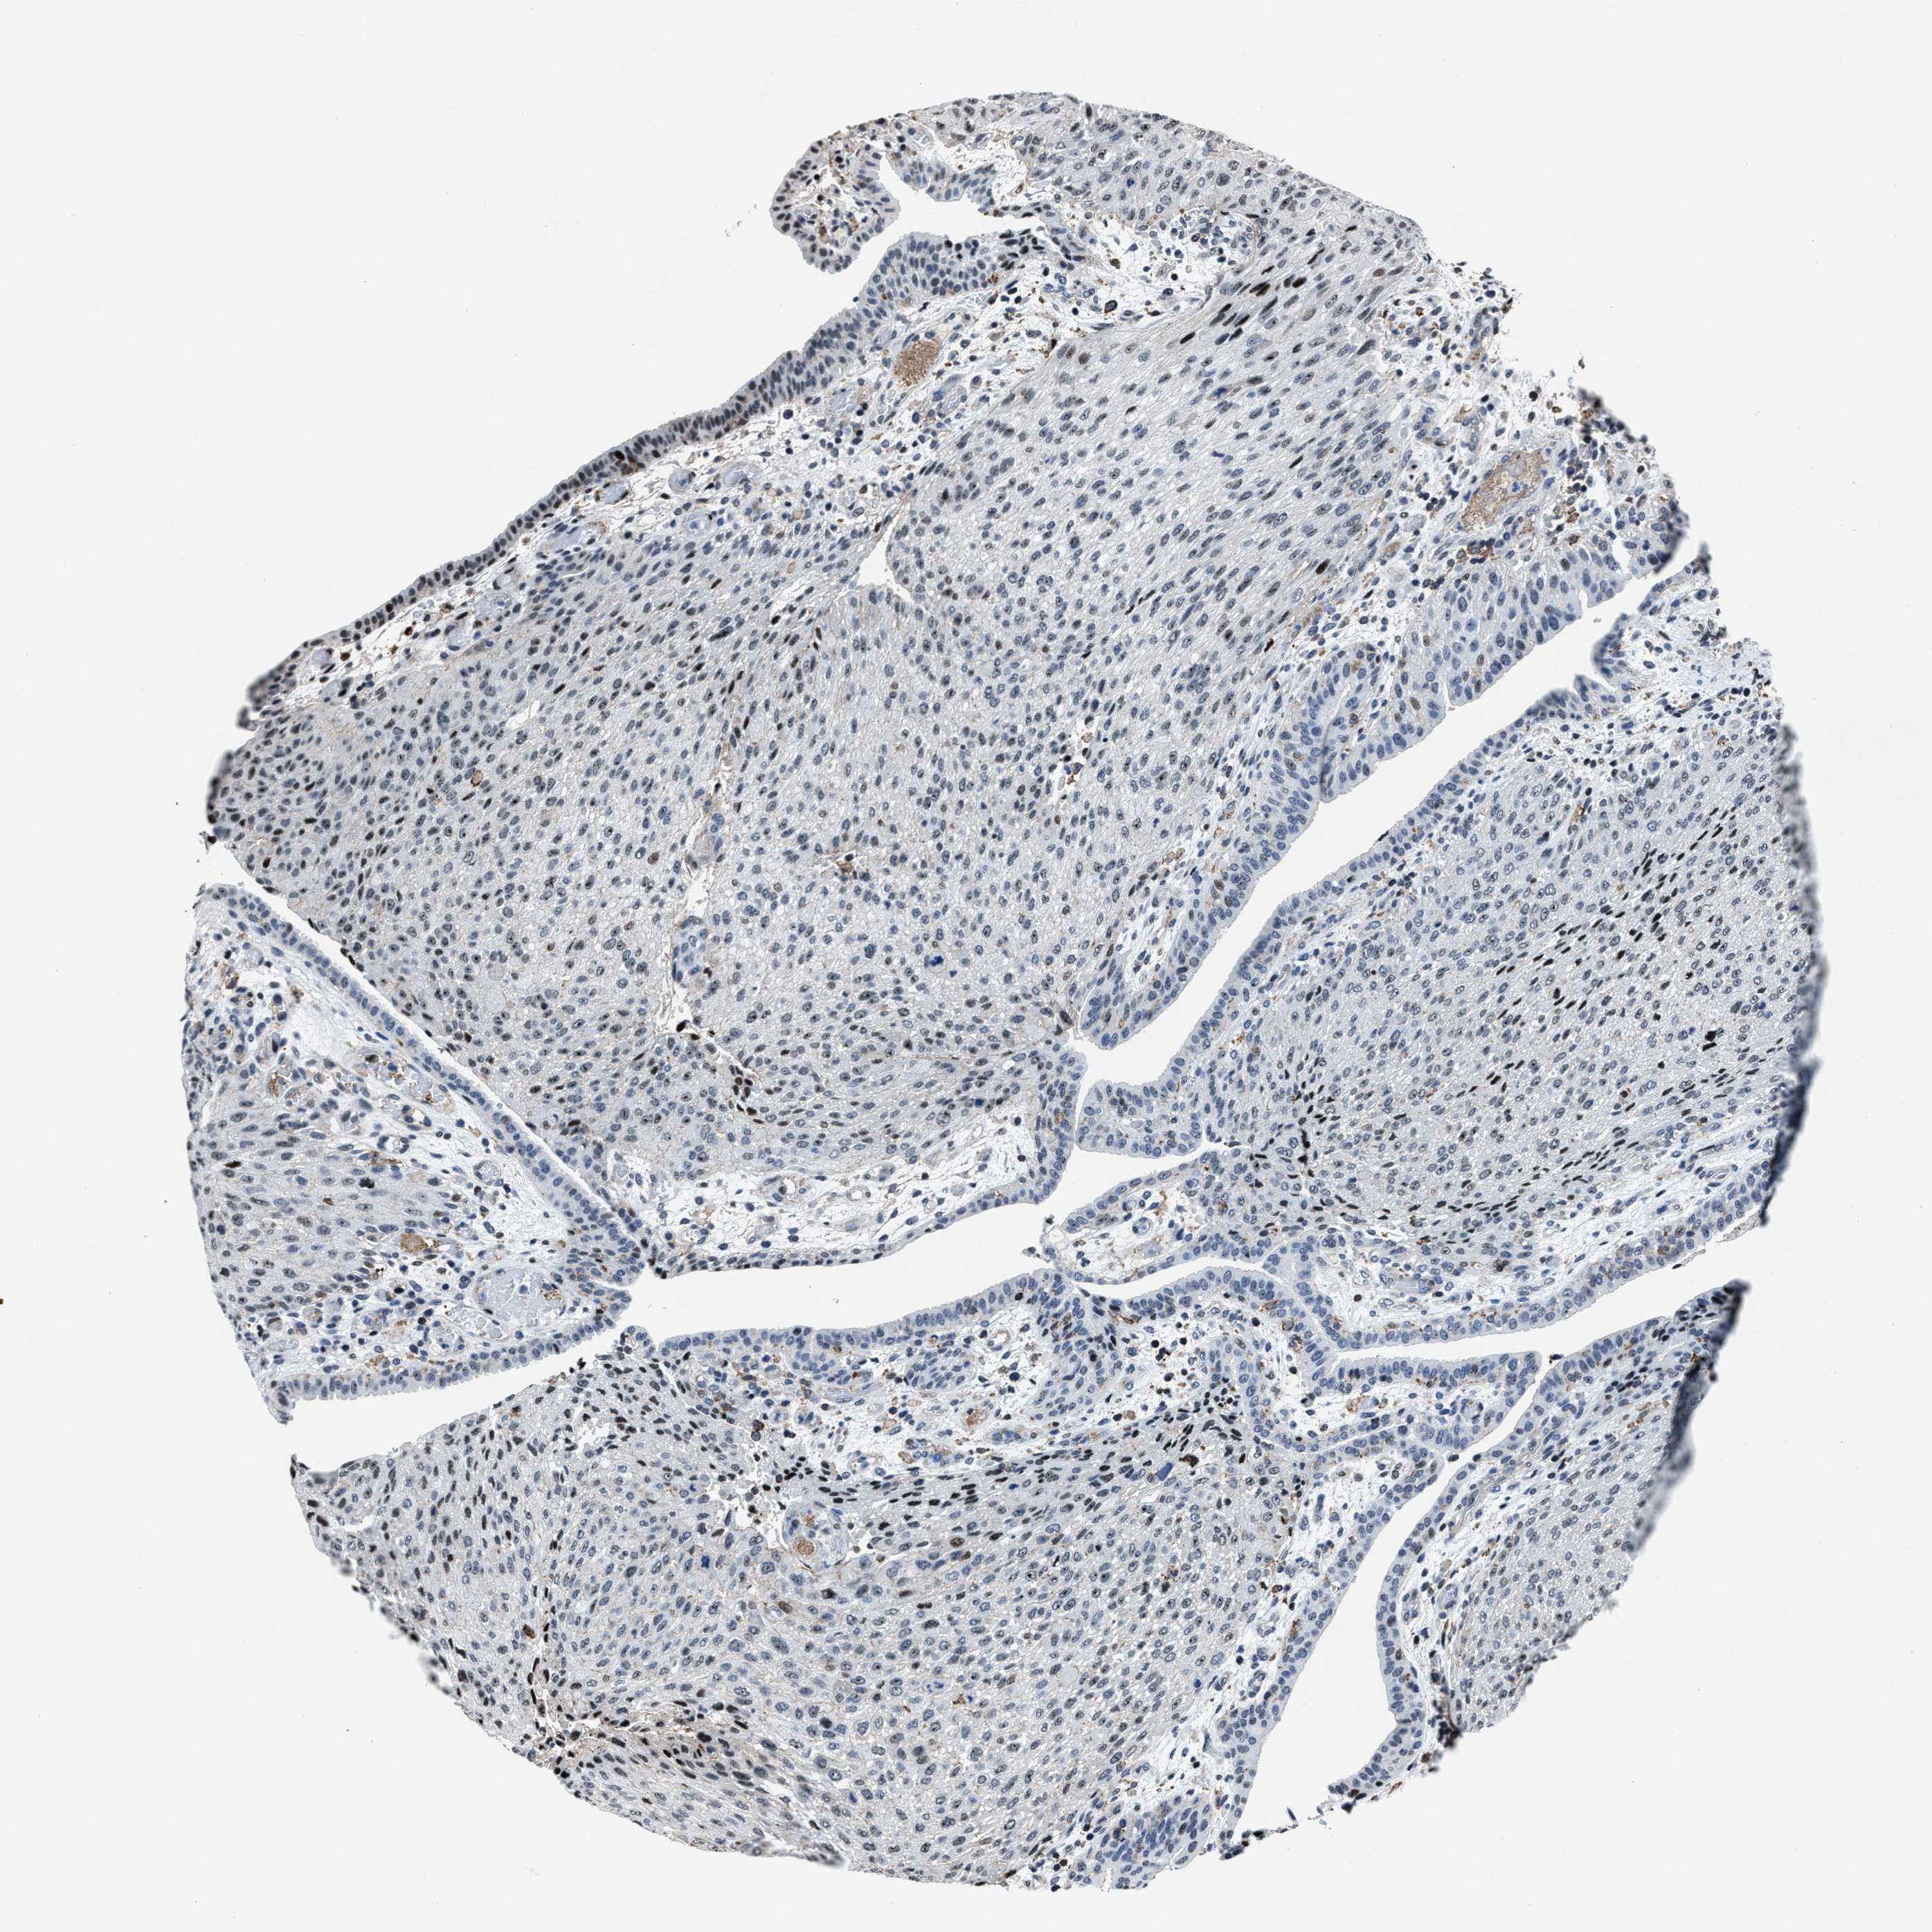

UROTHELIAL CANCER - Protein expressioni

A mouse-over function shows sample information and annotation data. Click on an image to view it in a full screen mode. Samples can be filtered based on level of antibody staining by selecting one or several of the following categories: high, medium, low and not detected. The assay and annotation is described here.

Note that samples used for immunohistochemistry by the Human Protein Atlas do not correspond to samples in the TCGA dataset.

Antibody stainingi

Antibody staining in the annotated cell types in the current human tissue is reported as not detected, low, medium, or high, based on conventional immunohistochemistry profiling in selected tissues. This score is based on the combination of the staining intensity and fraction of stained cells.

Each image is clickable and will lead to virtual microscopy that enables deeper exploration of all samples and also displays staining intensity scores, fraction scores and subcellular localization as well as patient and tissue information for each sample.

Antibody HPA020131

Staining

High

Medium

Low

Not detected

Intensity

Strong

Moderate

Weak

Negative

Quantity

>75%

75%-25%

<25%

None

Location

Urothelial carcinoma, Low grade

Urothelial carcinoma, High grade